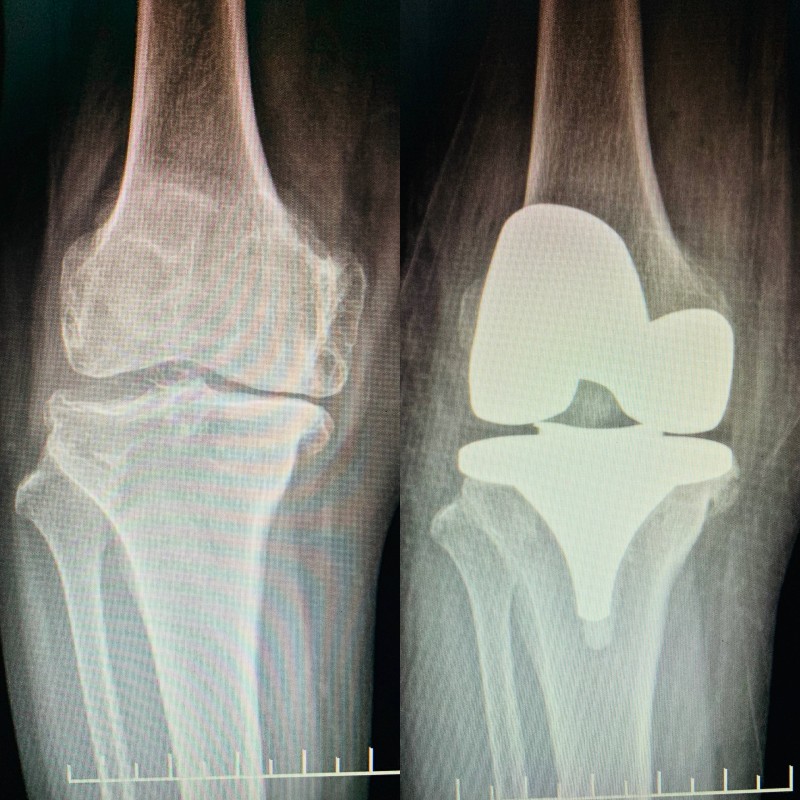

(膝關節(jié)置換術前術后對比)